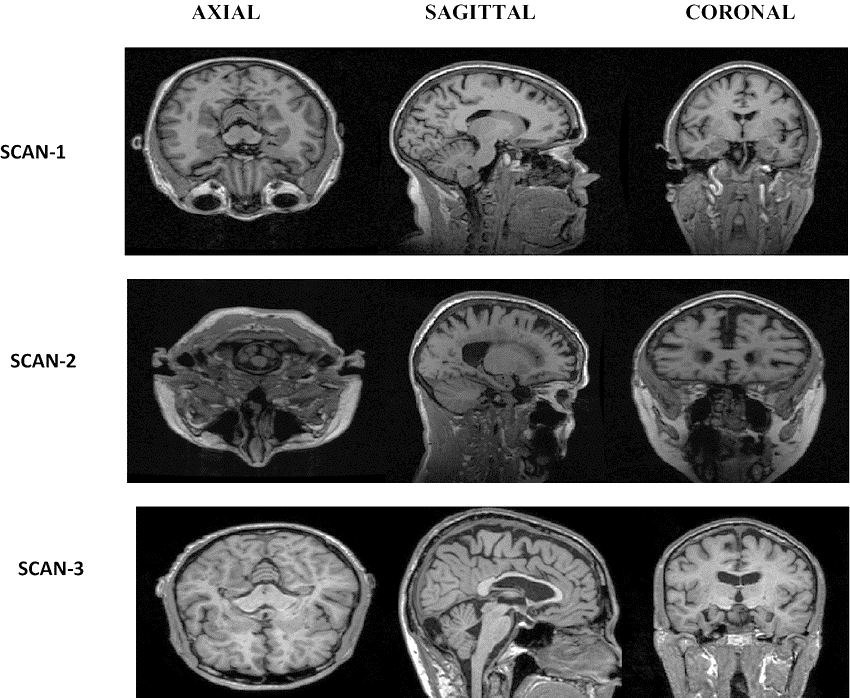

The data for both datasets is in NIFTI format with a file extension of .nii. MRI data provides detailed information about the brain, including its anatomy in all three planes: Axial, sagittal, and coronal (Figure 3). It should be noted that MRI data can be used to visualize the brain in all three planes, allowing for a comprehensive understanding of its structure and any potential abnormalities.

XXXXXXXX

Fig. 3. MRI image Planes.